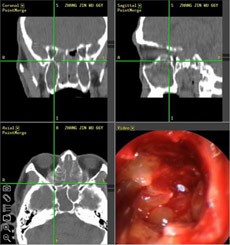

经推荐,跨省来到西安新城中大耳鼻喉医院耳鼻喉科治疗,入院后,经医生诊断并推荐使用“”,在鼻内窥镜的帮助下切除鼻息肉,术后经过10天后复诊并无复发现象。

(图为:鼻窦炎患者治疗现场)                          (图为:鼻窦炎治疗图谱)